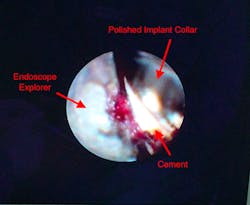

The dental endoscope is invaluable for preventing and treating peri-implantitis. The endoscope allows for visualization of residual cement, microgaps, and open and overhanging crown margins (figure 3). Inspection with the endoscope at the time of restoration can be a kind of insurance policy for the doctor to be sure that any conditions that would cause iatrogenic problems are not present (figure 4).

Figure 3: A dental implant with residual cement, as seen through the dental endoscope